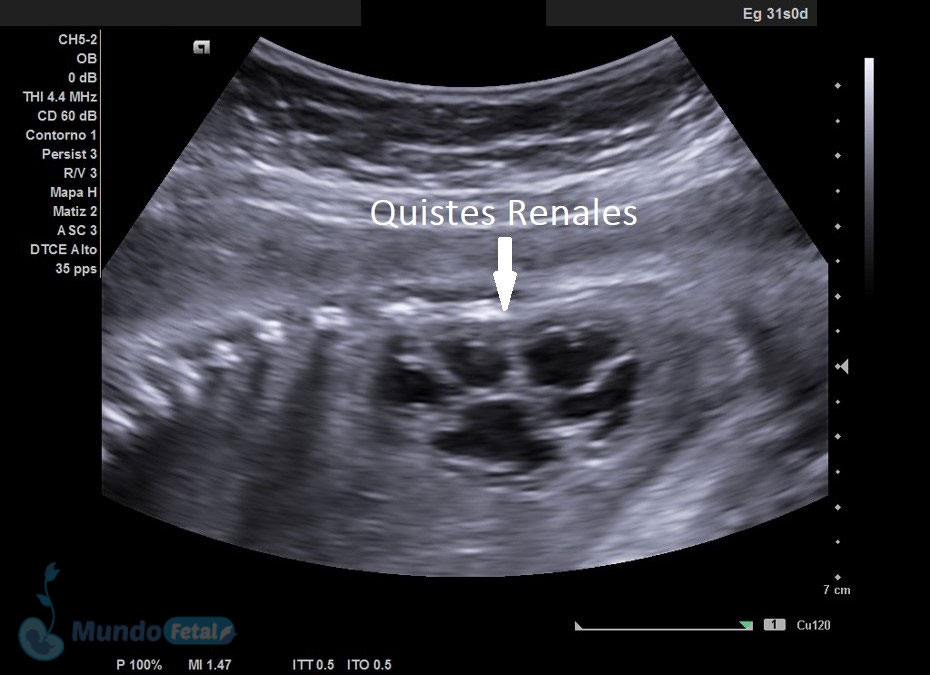

Ultrasonido Nivel II, Patología Fetal

Estudio llevado a cabo en todo bebe, en quien se haya detectado alguna alteración anatómica o marcador de riesgo, valorando todos sus órganos, aparatos y sistemas, de manera específica y detallada.